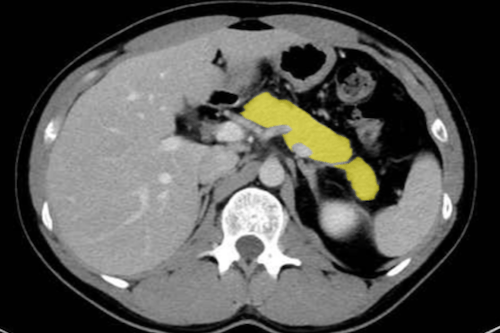

3. 췌장·비장 질환

췌장과 비장은 복부 CT에서 조영제를 이용해 세밀히 평가됩니다.

- 급성 췌장염: 췌장 비후, 주변 지방 침윤, 복강 내 액체 저류 등이 전형적인 CT 소견입니다. 중증일 경우 괴사성 변화와 농양 형성이 관찰됩니다.

- 만성 췌장염: 석회화, 췌관 확장, 위축된 췌장 등이 나타납니다.

- 췌장암: 주로 췌장두부에 발생하며, 담도 폐쇄로 인한 황달을 유발합니다. 조영 CT로 종양 크기, 혈관 침범, 간·림프절 전이를 평가할 수 있습니다.